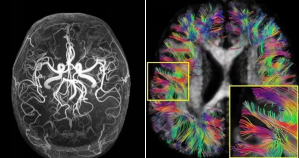

5.0T超高场高分辨成像效果(左:血管成像;右:脑神经纤维束成像)

国际首创5.0T超高场全身磁共振

医工所影像中心磁共振成像团队针对我国高端磁共振装备严重依赖进口、核心技术创新乏力的困境,聚焦原始技术创新、成像理论、关键部件和装备研发及生物医学应用,与上海联影公司合作研制出我国首台3.0T和世界首台超高场人体全身临床磁共振,构建了大型成像设备“自主创新-国产制造-临床应用”全链条融通创新体系。2022年8月,联影5.0T产品取得国家医疗器械注册证,在3T以上人体全身磁共振成像的国际空白持续了20余年之后,双方合作填补了这一空白,在临床使用中展示出超越现有顶级产品的图像质量及诊断能力,实现尖端成像设备自主创新的跨越与引领,具有重大的经济与社会价值。